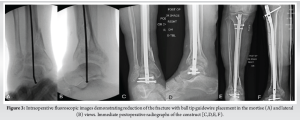

The tibiotalar nail was performed in the supine position on a radiolucent bed. The suprapatellar approach for tibial nailing was utilized. The fracture was closed reduced with manual manipulation and traction, ensuring to keep the talus centered below the tibia on a mortise and lateral fluoroscopic views. The ankle joint was maintained in neutral dorsiflexion and 5° of external rotation and valgus. The guidewire was then inserted down into the talus, and the canal was sequentially reamed. Of note, the patient had very osteopenic bone quality allowing for direct impaction of the ball-tipped guide wire into the talus. A threaded guidewire can be introduced in a retrograde manner through the calcaneus and into the talus for cases with more dense talar bone stock. We chose to utilize an 8 mm nail in order to preserve bone stock if a hindfoot nail was needed in the future. The ankle joint was not prepped for a fusion to preserve motion if the patient wished to have the nail removed in the future, once the fracture healed. Two interlocking screws were placed distally and three placed proximally (Fig. 3). She was placed into a posterior slab splint and made non-weight bearing for 6 weeks.